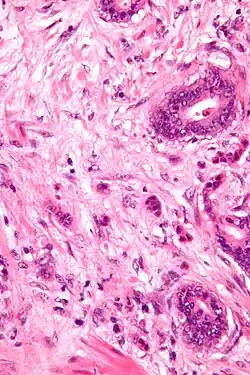

Tumor budding is loosely defined by the presence of individual cells and small clusters of tumor cells at the invasive front of carcinomas. It has been postulated to represent an epithelial–mesenchymal transition (EMT).

Tumor budding is a well-established independent adverse prognostic factor in colorectal carcinoma that may allow for stratification of patients into risk categories more meaningful than those defined by TNM staging, and also potentially guide treatment decisions, especially in T1 and T3 N0 (Stage II, Dukes’ B) colorectal carcinoma. Unfortunately, its universal acceptance as a reportable factor has been held back by a lack of definitional uniformity with respect to both qualitative and quantitative aspects of tumor budding.[1]